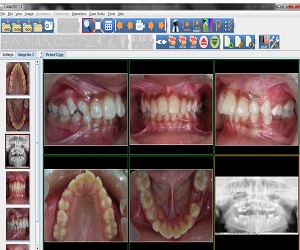

CollabDDS provides a real time collaborative environment to visualize medical (Skeletal) and dental images (digitized X-Ray images or DICOM data) for diagnosis and treatment planning. CollabDDS has various image processing tools to visualize the data and also annotate. An inbuilt repository of annotated images can be used for education. Further it enables real time collaboration for diagnosis between physician at PHC level and experts at medical colleges and hospitals. CollabDDS is unique as it allows the viewing and processing of digitized X-Rays in various standard image formats like JPEG and DICOM and also allows this data to be saved for later review/ study.

With the proof of concept having gone through successfully, a Pilot Project for Implementation of CollabDDS at Medical and Dental Colleges and Hospitals has been undertaken. This is an extension of the POC to the Operational Research Phase as a prelim to rollout. This pilot implementation is used to evaluate the efficiency and effectiveness of remote diagnosis. Further this phase also incorporates a module which carries out Cephalometric analysis for orthodontic surgeons to enable diagnosis and treatment planning of their patients. This phase would also include the Enhancement of CollabDDS and Advanced Applications on 3D imaging. It would involve the reconstruction of 3-D models from CT / Surface images, development of methodologies for orthopedic implant development using 3D models.